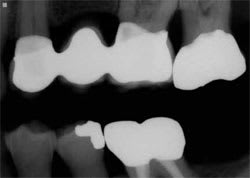

Figure 5 Case 2, preoperative condition. | Figure 6 Case 2, prepared and isolated. | ||||||

Clinical findings:Tooth No. 13 was missing. Flexible unilateral replacement supported entirely by the soft tissue. Tooth Nos. 12 and 14 provided stability. Gingival recession was evident on the palatal of teeth Nos. 12 and 14 secondary to trauma from a tissue-borne removable partial denture. Tooth No. 12 had been restored with a mesial-occlusal composite resin with evidence of a crack through the distal marginal ridge. Tooth No. 14 had been restored with a full gold crown.

Radiographic findings: There was a normal periapical appearance of teeth Nos. 12 and 14. The maxillary sinus location prevented implant placement without grafting. Bone loss was evident on distal tooth No. 14.